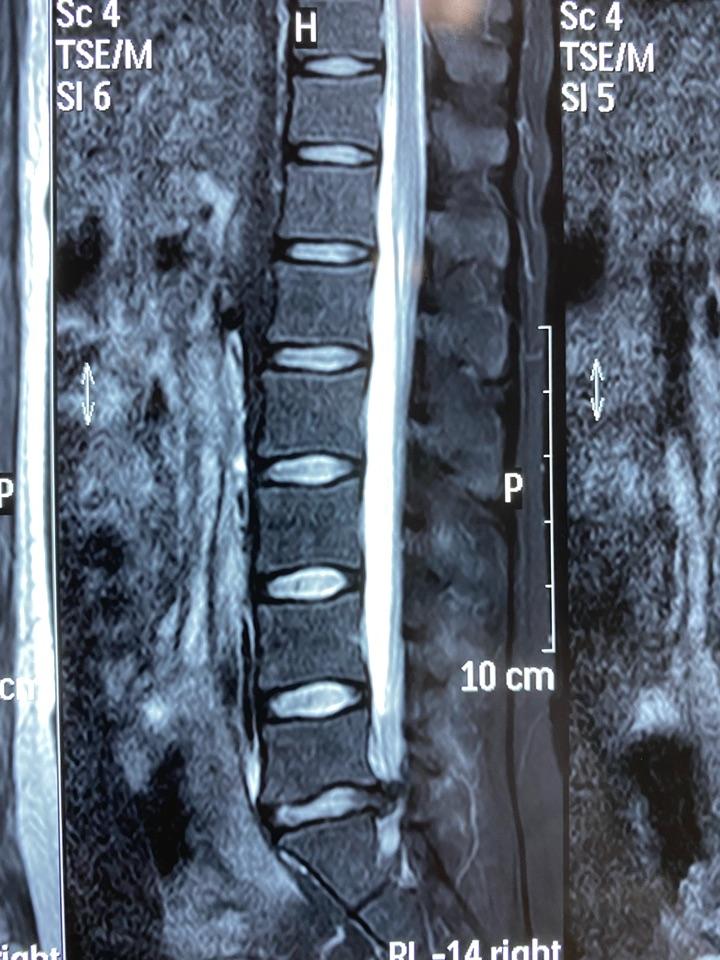

腰椎磁共振:腰5-骶1椎间盘脱出占满椎管,硬膜囊受压继发椎管狭窄